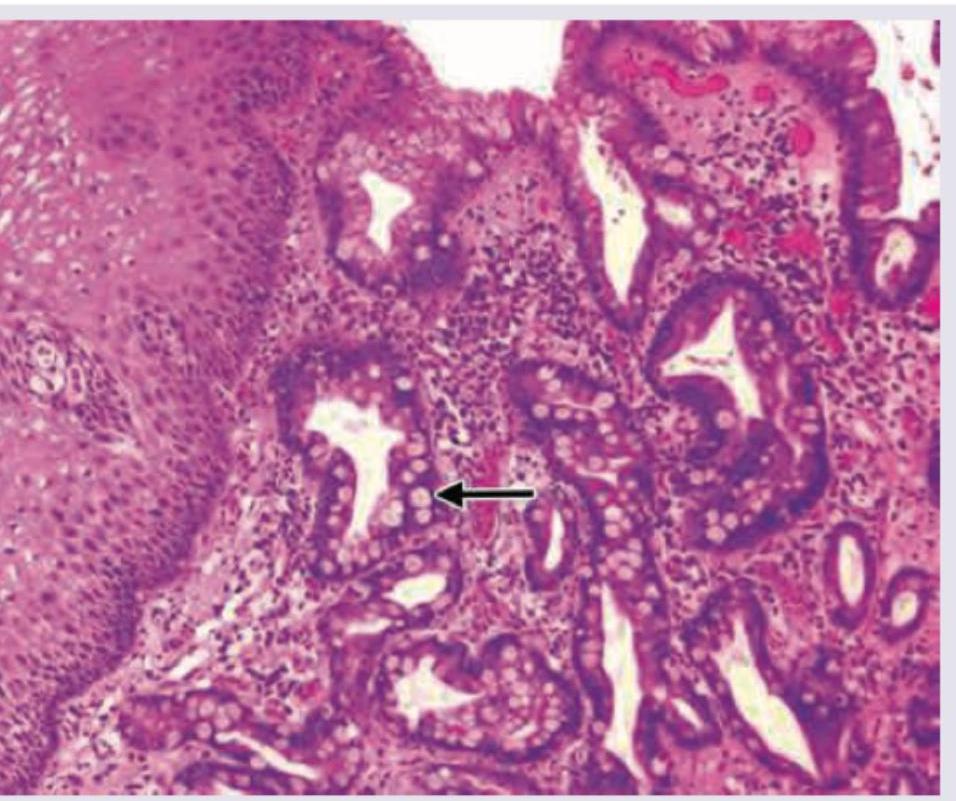

A 40-year-old patient presents with heart burn and increased salivation. UGI endoscopy was performed and biopsy was taken. What is the diagnosis? (AIIMS May 2017)

Explanation: ***Barrett's esophagus*** - The symptoms of **heartburn** and **increased salivation** are classic for **gastroesophageal reflux disease (GERD)**, which is the primary risk factor for Barrett's esophagus. - **Biopsy** is crucial for diagnosing Barrett's esophagus [2], which is characterized by the replacement of normal **squamous epithelium** with **specialized intestinal metaplasia** in the distal esophagus [1]. *Esophagitis* - While **esophagitis** (inflammation of the esophagus) can cause heartburn, it is a broader term and does not specifically describe the **metaplastic change** seen on biopsy. - Esophagitis can be caused by various factors (e.g., reflux, infections, eosinophilic), and without the specific biopsy finding of **intestinal metaplasia** [1], it's not the most precise diagnosis. *Adenocarcinoma esophagus* - **Adenocarcinoma of the esophagus** typically arises from **Barrett's esophagus** [1], but the question implies a diagnosis based on the initial presentation and biopsy, not necessarily a malignant transformation yet. - While Barrett's esophagus is a **pre-malignant condition** [1], the biopsy finding would specifically state adenocarcinoma if it were present, not just the changes leading to it. *Squamous cell carcinoma esophagus* - **Squamous cell carcinoma** is more commonly associated with risk factors like **smoking** and **alcohol consumption**, and typically arises from the **squamous epithelium** of the esophagus, not from metaplastic changes. - The symptoms of heartburn and increased salivation are more indicative of reflux-related changes, which predispose to adenocarcinoma via Barrett's, rather than squamous cell carcinoma. **References:** [1] Cross SS. Underwood's Pathology: A Clinical Approach. 6th ed. Common Clinical Problems From Alimentary System Disease, pp. 348-349. [2] Kumar V, Abbas AK, et al.. Robbins and Cotran Pathologic Basis of Disease. 9th ed. The Gastrointestinal Tract, pp. 764-765.